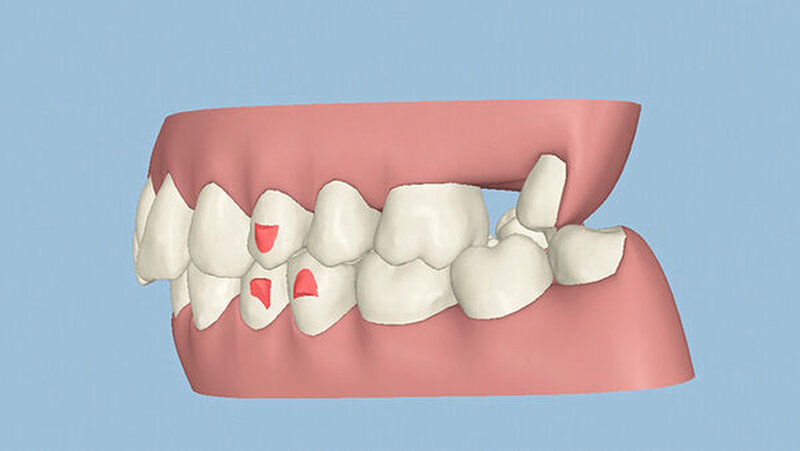

Kieferorthopädisch imponierte beidseits eine neutrale Verzahnung bei einem tiefen Biss von 5 mm – bedingt durch die Verlängerung beider Frontzahngruppen. Besonders Zahn 11 zeigte eine erhebliche Verlängerung und Protrusion mit einer sagittalen Frontzahnstufe von 5 mm. Sowohl die Frontzähne im Ober- als auch im Unterkiefer wiesen eine lückige Beziehung zueinander auf (Abbildung 1).

Die Sulkustiefen konnten auf etwas weniger als 4 mm reduziert werden, während der Blutungs- und Plaque-Index bei weniger als 15 Prozent lag. Daher wurde eine kieferorthopädische Behandlung über die nächsten zwei Jahre in Kombination mit engen zahnärztlichen Kontrollen geplant. Als Mittel der Wahl entschieden wir uns gemeinsam mit dem Patienten für das Invisalign-System, da hiermit sowohl eine Schienung als auch eine kraft-arme Bewegung der Zähne möglich sein sollte. Für den Frontzahnbereich wurden keine Attachments geplant, so dass hier eine unnötige Hebelwirkung umgangen werden konnte (Abbildung 3).